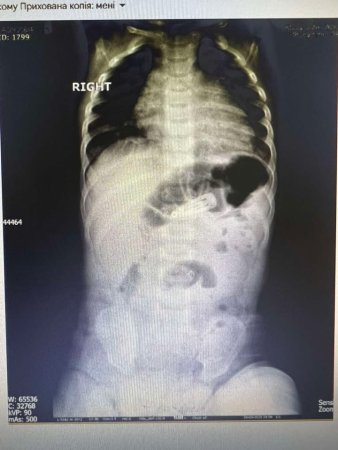

Унікальний медичний випадок стався в Мукачеві: в обласній дитячій лікарні лікарі провели ендоскопічне видалення заколки для волосся зі шлунка 6-місячної дитини. Це перша така процедура на Закарпатті, виконана без відкритого хірургічного втручання, що могло б становити загрозу для життя малюка через його вік і вагу.